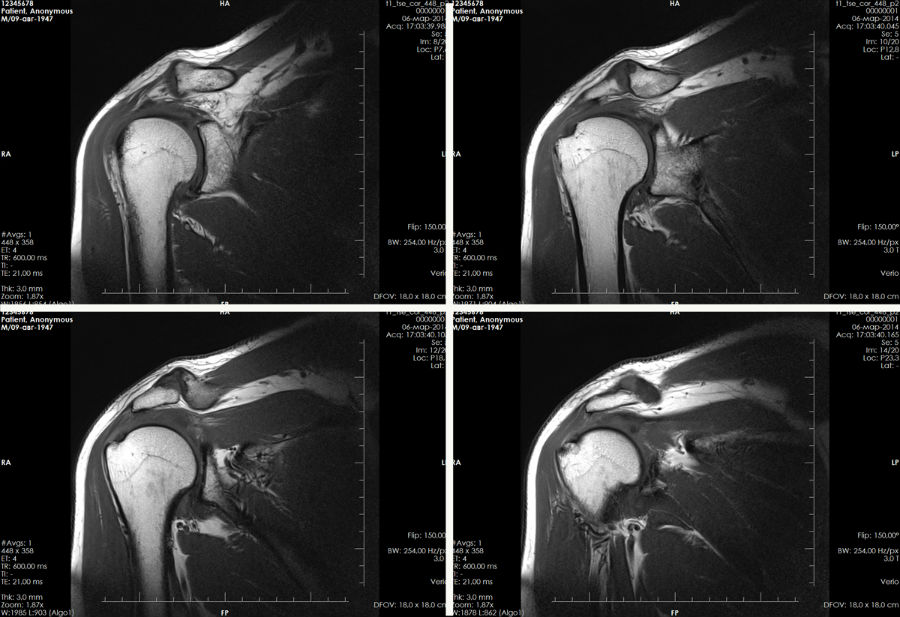

Дополнительно могут быть проведены УЗИ, МРТ и артроскопия. Также назначаются другие исследования для исключения различных патологий опорно-двигательного аппарата.